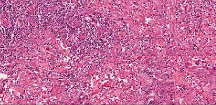

We have compared our approach against three image restoration approaches: DeblurGAN-v2 [7], SRGAN [8], and Real-ESRGAN [15]. DeblurGAN corrects for Gaussian and motion blur (similar to Restore-GAN) where as SRGAN and Real-ESRGAN upsample images to 4X similar to what we are doing in this work (10X to 40X). As shown in the comparisons below in Figure 3, our model achieved better performance against these methods when run on real microscope video imagery. In particular, DeblurGAN and SRGAN show little to no visual improvement to the input images. Real-ESRGAN sharpens the image where there is sufficient contrast, but does not restore or enhance areas of low contrast.

The key difference between these other methods and our method is that we train on image data captured from real low quality videos and corresponding high quality scanned images. These videos contain natural variations in focus and illumination, which cause real world blur and brightness/contrast changes across different frames. Other models are trained on synthetic Gaussian and motion blur, which are not representative of the more complex distortions seen in real world data. Their training data also starts as high quality data, while we train with true lower quality image data that contains all defects found in real world video captured from microscopes.

We demonstrate our WSI creation workflow on Leishmaniasis cases, as shown in Figures 1 and 4. An expert pathologist reviewed the cases and annotated granulomas as well as LD bodies on the stitched images and our generated images in Figure 4. To show generalizability of our approach, we also show results on core biopsies of breast, duodenum, stomach, liver, and lymph nodes (Figure 5).